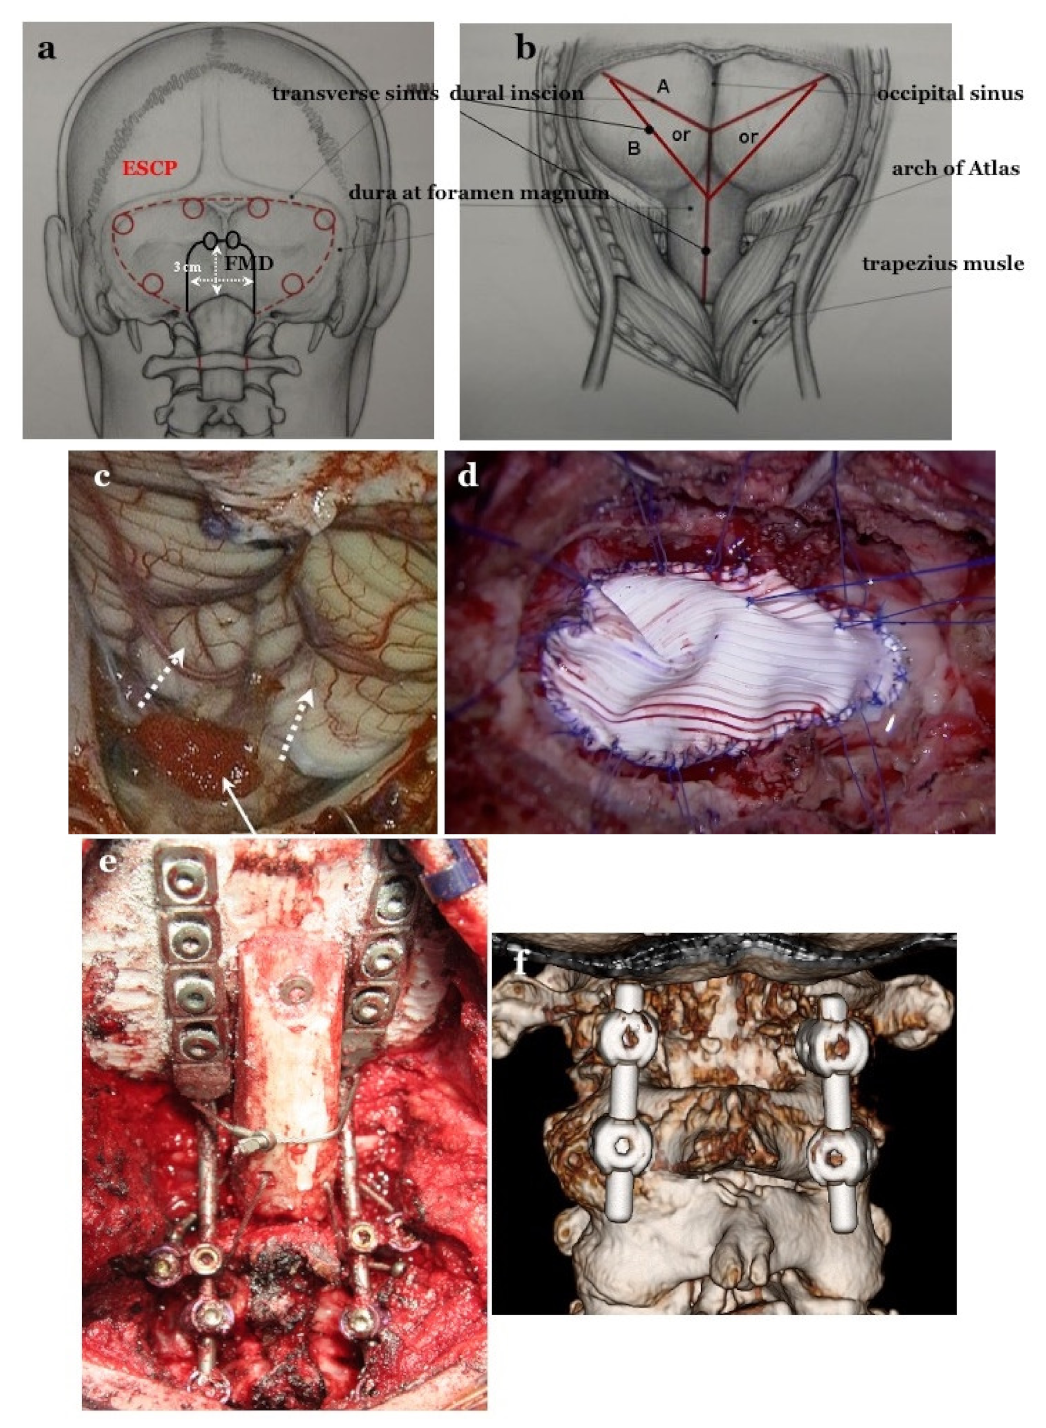

2.4.1. Foramen Magnum Decompression (FMD) for CM-I Type B and CM-Borderline

2.4.2. Expansive Suboccipital Cranioplasty (ECSP) for CM-I Type C

2.4.3. CCF for CM-I with CCJ Instability